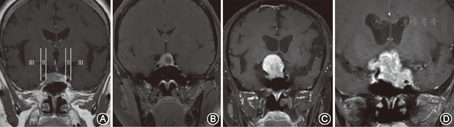

患者术前均经蝶窦冠状面CT、蝶鞍区增强MR检查,术后复查MR。肿瘤位于鞍内,或侵犯至蝶窦内或鞍上,最大径0.6~4.1 cm。其中微腺瘤24例(< 1 cm),大腺瘤81例(1~4 cm),巨腺瘤11例(> 4 cm)。垂体瘤卒中16例。如图1所示,取蝶鞍区MR冠状位T1增强相,以双侧颈内动脉(床突段)内、外缘所在矢状面分隔,将鞍上分为Ⅰ、Ⅱ、Ⅲ三区,肿瘤一侧仅位于1个分区者(定义为A类,包括左Ⅰ右Ⅰ、左Ⅰ右Ⅱ、左Ⅰ右Ⅲ、左Ⅱ右Ⅰ、左Ⅲ右Ⅰ)71例,双侧均侵犯至Ⅲ区者(定义为C类:左Ⅲ右Ⅲ)11例,其余(定义为B类:左Ⅱ右Ⅱ、左Ⅱ右Ⅲ、左Ⅲ右Ⅱ)34例。

经典的经单鼻孔蝶窦入路:上述A类肿瘤采用此入路方式,示意如图2。患者仰卧位,头略左偏右旋,面部及鼻腔消毒,肾上腺素棉片收敛双侧鼻腔黏膜,扩大中、上鼻甲与鼻中隔的距离。根据肿瘤偏移的左右方位选择相反的鼻孔为主要入路,即:肿瘤偏左则自右鼻孔进镜,偏右则自左鼻孔进镜。在内镜下依次辨认后鼻孔、中鼻甲后端、上鼻甲及蝶筛隐窝及蝶窦开口[8]。在鼻中隔后端骨-软骨交界处黏膜做弧形切口,将黏膜向后外翻,鼻中隔前端向对侧推移,暴露双侧蝶窦前擘及鼻中隔后端,用磨钻磨除部分骨性鼻中隔骨质(<15 mm)[9]及蝶窦前壁,辨认颈内动脉隆起[10]。参考蝶窦冠扫CT磨除蝶窦间隔,根据磁共振显示的鞍底形态磨除鞍底骨质,磨开位置在鞍底中间偏下方。细针穿刺确认无出血或脑脊液漏后,切开鞍底硬膜进入鞍区,在0°、30°内镜下用取瘤钳、刮匙及吸引器分块或完整切除肿瘤,内镜探察瘤腔及其周围结构,尤其是鞍旁、鞍上区,辨认正常结构和肿瘤组织,进一步切除残余肿瘤。瘤腔填塞速即纱及明胶海绵,人工硬膜封闭鞍底。如果鞍隔已破,术中存在脑脊液漏,则以自体筋膜或鼻腔黏膜瓣修补鞍底[11],以导尿管球囊适当压迫限位促进愈合。复位鼻中隔,进镜鼻孔膨胀海绵填塞。(1)经双鼻孔蝶窦入路:前述C类肿瘤采用此入路方式,示意如图2。准备工作同前,在内镜下辨认双侧蝶窦开口,分别在双侧鼻中隔骨-软骨交界处弧形切开黏膜,向两侧翻起至蝶窦开口外侧,暴露双侧蝶窦前壁,磨钻磨除骨质[12],内镜、吸引器、刮匙或其他器械分别自双侧任意鼻孔进入术野,更换应用不同工作角度达到尽可能切除肿瘤之目的。(2)"一侧半"——对侧鼻中隔黏膜切开辅助下的经单鼻孔蝶窦入路:本组前述B类肿瘤采用此入路方式,示意如图2。准备工作同经典入路,在完成一侧黏膜翻起、蝶窦前壁骨质磨除后,于已磨除的骨性鼻中隔旁黏膜处仅以单极电刀开一小口,不向外翻起黏膜,自非主入路鼻孔置入器械(刮匙、取瘤钳等),穿过小口,到达术野(矢状面直视效果见图3)。获得更广的工作角度,尽可能全切肿瘤。手术结束行双侧鼻腔填塞,减少术后粘连和鼻腔不适,增加鼻腔气流量[13]。